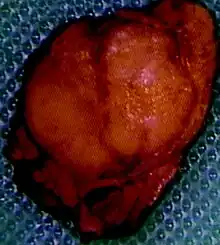

| Pathology of pancreatic endocrine tumour (insulinoma). | |